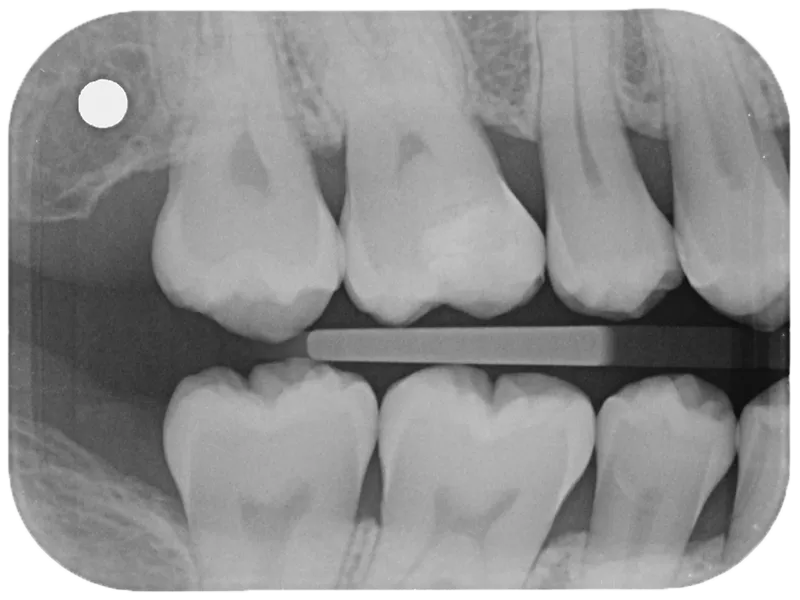

The X-ray reveals a well-adapted, conservatively placed restoration with optimal translucency for a more natural radiographic appearance.